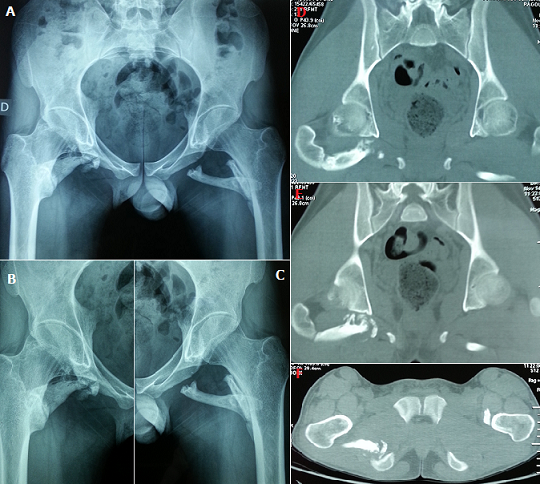

La myosite ossifiante circonscrite est une affection bénigne caractérisée par une prolifération hétérotopique d'os dans les tissus mous. Elle survient généralement chez des adolescents ou de jeunes adultes. De très rares cas ont été décrits chez les enfants. Son étiopathogénie n'est pas claire, il semble toutefois qu'un foyer de nécrose musculaire ou un hématome puissent être à l'origine de la lésion. Les sièges les plus fréquents sont le quadriceps et le biceps brachial. Nous présentons le cas d'un patient âgé de vingt ans, aux antécédents d'hémophilie A, admis dans notre service de Médecine Physique et de Réadaptation Fonctionnelle pour prise en charge d'une limitation de la mobilité des deux hanches. L'histoire remonte à un an où le patient a présenté suite à une chute de sa propre hauteur avec réception sur les hanches une douleur et une tuméfaction à leur niveau. L'évolution était marquée par l'installation progressive d'une limitation de la mobilité des deux hanches responsable d'une gêne fonctionnelle et d'une réduction du périmètre de marche. L'examen clinique objectivait une limitation douloureuse de la mobilité des deux hanches sans autre signe accompagnateur. Les radiographies standards et le scanner du bassin ont montré une ossification musculaire autour des deux hanches, aspect compatible avec une myosite ossifiante progressive des muscles carrés fémoraux des deux côtés et du jumeau inférieur droit (A, B, C, D, E, F). Une intervention chirurgicale a été proposée mais refusée par le patient. Il a alors bénéficié d'un traitement médical et de rééducation à visée antalgique. L'évolution était marquée par une légère amélioration fonctionnelle.